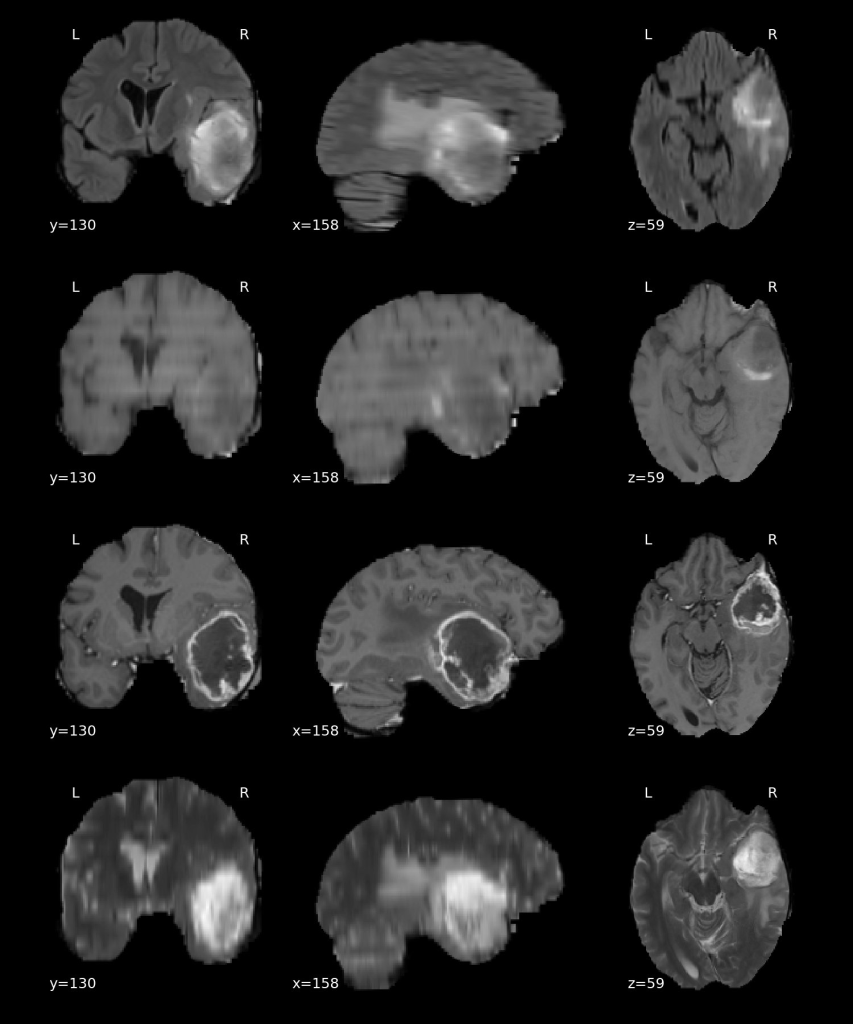

We used a multi-modal MRI brain tumor image segmentation benchmark dataset named BraTS. The MRI imaging sequences included in this dataset are T2-FLAIR, T1, T1Gd, and T2-weighted (Figure 1). The four modalities are concatenated as the fourth dimension (channel) on top of the X, Y, and Z dimensions. There are 750 patients (484 training and 266 testing) from BraTS’16 and ’17. The target of this dataset is to segment gliomas tumors and subregions. The tumor can also be partitioned as peritumoral edema, GD-enhancing tumor, and the necrotic (or non-enhancing) tumor core (Figure 2). The tumor can also be delineated as a whole tumor (WT), tumor core (TC), and enhancing tumor (ET) (Figure 2), which is the label definition we used in this work. Human expert annotation is conducted and provided within the dataset. This dataset is provided by Medical Segmentation Decathlon, and can be downloaded from the AWS Open Data Registry.

Figure 1. Multi-modality tumor dataset BraTS. From top to bottom: T2-FLAIR, T1, T1Gd, and T2-weighted. All four modalities provide complementary information for identifying tumor regions. Case BraTS_001.